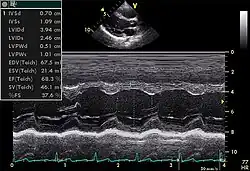

Le cœur est un organe tridimensionnel mobile. La prise en compte de cette quatrième dimension (le temps) est nécessaire pour une bonne appréhension de l'organe dans sa globalité. Cela nécessite une résolution temporelle suffisante pouvant être caractérisée par la cadence d'acquisition des images : elle doit être au moins d'une vingtaine images/s et idéalement supérieure à 50 images/s (pour permettre une visualisation correcte en ralenti, surtout si la fréquence cardiaque est élevée). De même, l'analyse à l'aide d'une image, par essence, bidimensionnelle, d'un organe quadridimensionnel, impose certains artifices : c'est le mode Tm (pour l' anglais : time motion), utilisé de manière courante, avec en abscisse le déroulement du temps et en ordonnée les échos détectés sur une seule ligne de tir.

- On en mesure les diamètres en systole et en diastole.

- On peut mesurer son volume, également en systole et en diastole : on somme le volume des disques successifs (de la pointe du cœur jusqu'à sa base) dont les diamètres sont estimés sur une coupe grand axe (Méthode de Simpson). En faisant le rapport (volume diastolique – volume systolique)/volume diastolique, on obtient la fraction d'éjection, indice important de la fonction contractile du muscle cardiaque.